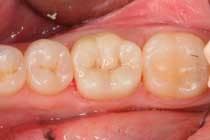

It truly is an exciting time to practice dentistry. There are so many advances that have impacted our collective dental practices that the art of dentistry has now blended with modern technology to provide an enjoyable dental experience for both clinician and patient. A dental visit can now be comfortable, efficient, and practical, in that a patient’s broken tooth can be permanently restored to optimal form, function, and esthetics in a single visit with a simple procedure (Figure 1).

The restoration of teeth in a single visit can now be measured in minutes instead of hours, and does not involve performing large, direct restorations that may not be clinically indicated and where the limits of the restorative materials are pushed. Indirect restorations can now be milled chairside from a solid, homogenous block of porcelain to restore the tooth to optimum fit, function, and esthetics (Figure 2).